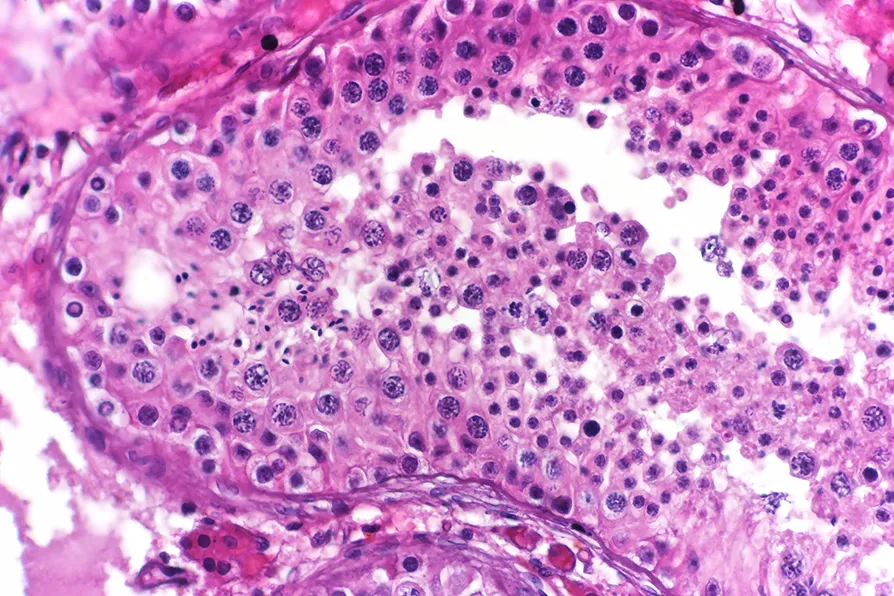

Most of these mutations are harmless, but some of them can have negative effects. For example, they can make a cell start to divide more quickly than it would otherwise, creating a lump of related cells that grows where it shouldn’t. This is the problem of cancer.

However, usually these mutations aren’t in the germline cells. So if a person with cancer has children, the changes that developed the cancer won’t be inherited by the next generation. But each time the germline blooms to make another body, new mutations could make cancer happen again.

These mutations are retained because of ongoing evolution inside the population of sperm cells. Natural selection within this population will favour sperm cells that are better at dividing more quickly, and over time these mutated sperm cells will have more descendants.

Unfortunately, these mutations are often associated with a higher rate of cancers and developmental disorders, which makes sense given the “cancer-like” property of faster division.

This means older sperm cells carry more risk of developmental disorders. The study’s estimate is that 3-5 per cent of sperm from men older than 50 carry a potentially dangerous mutation.